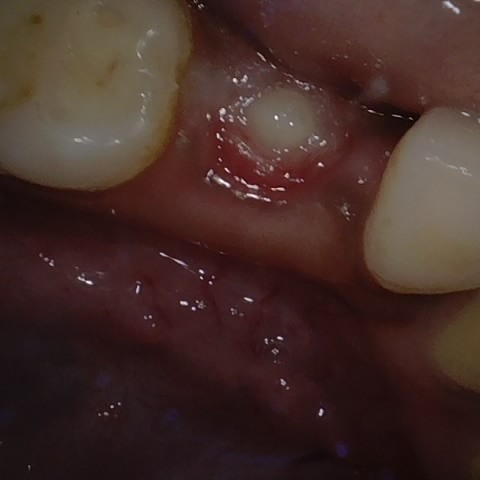

Annotated as "Good"